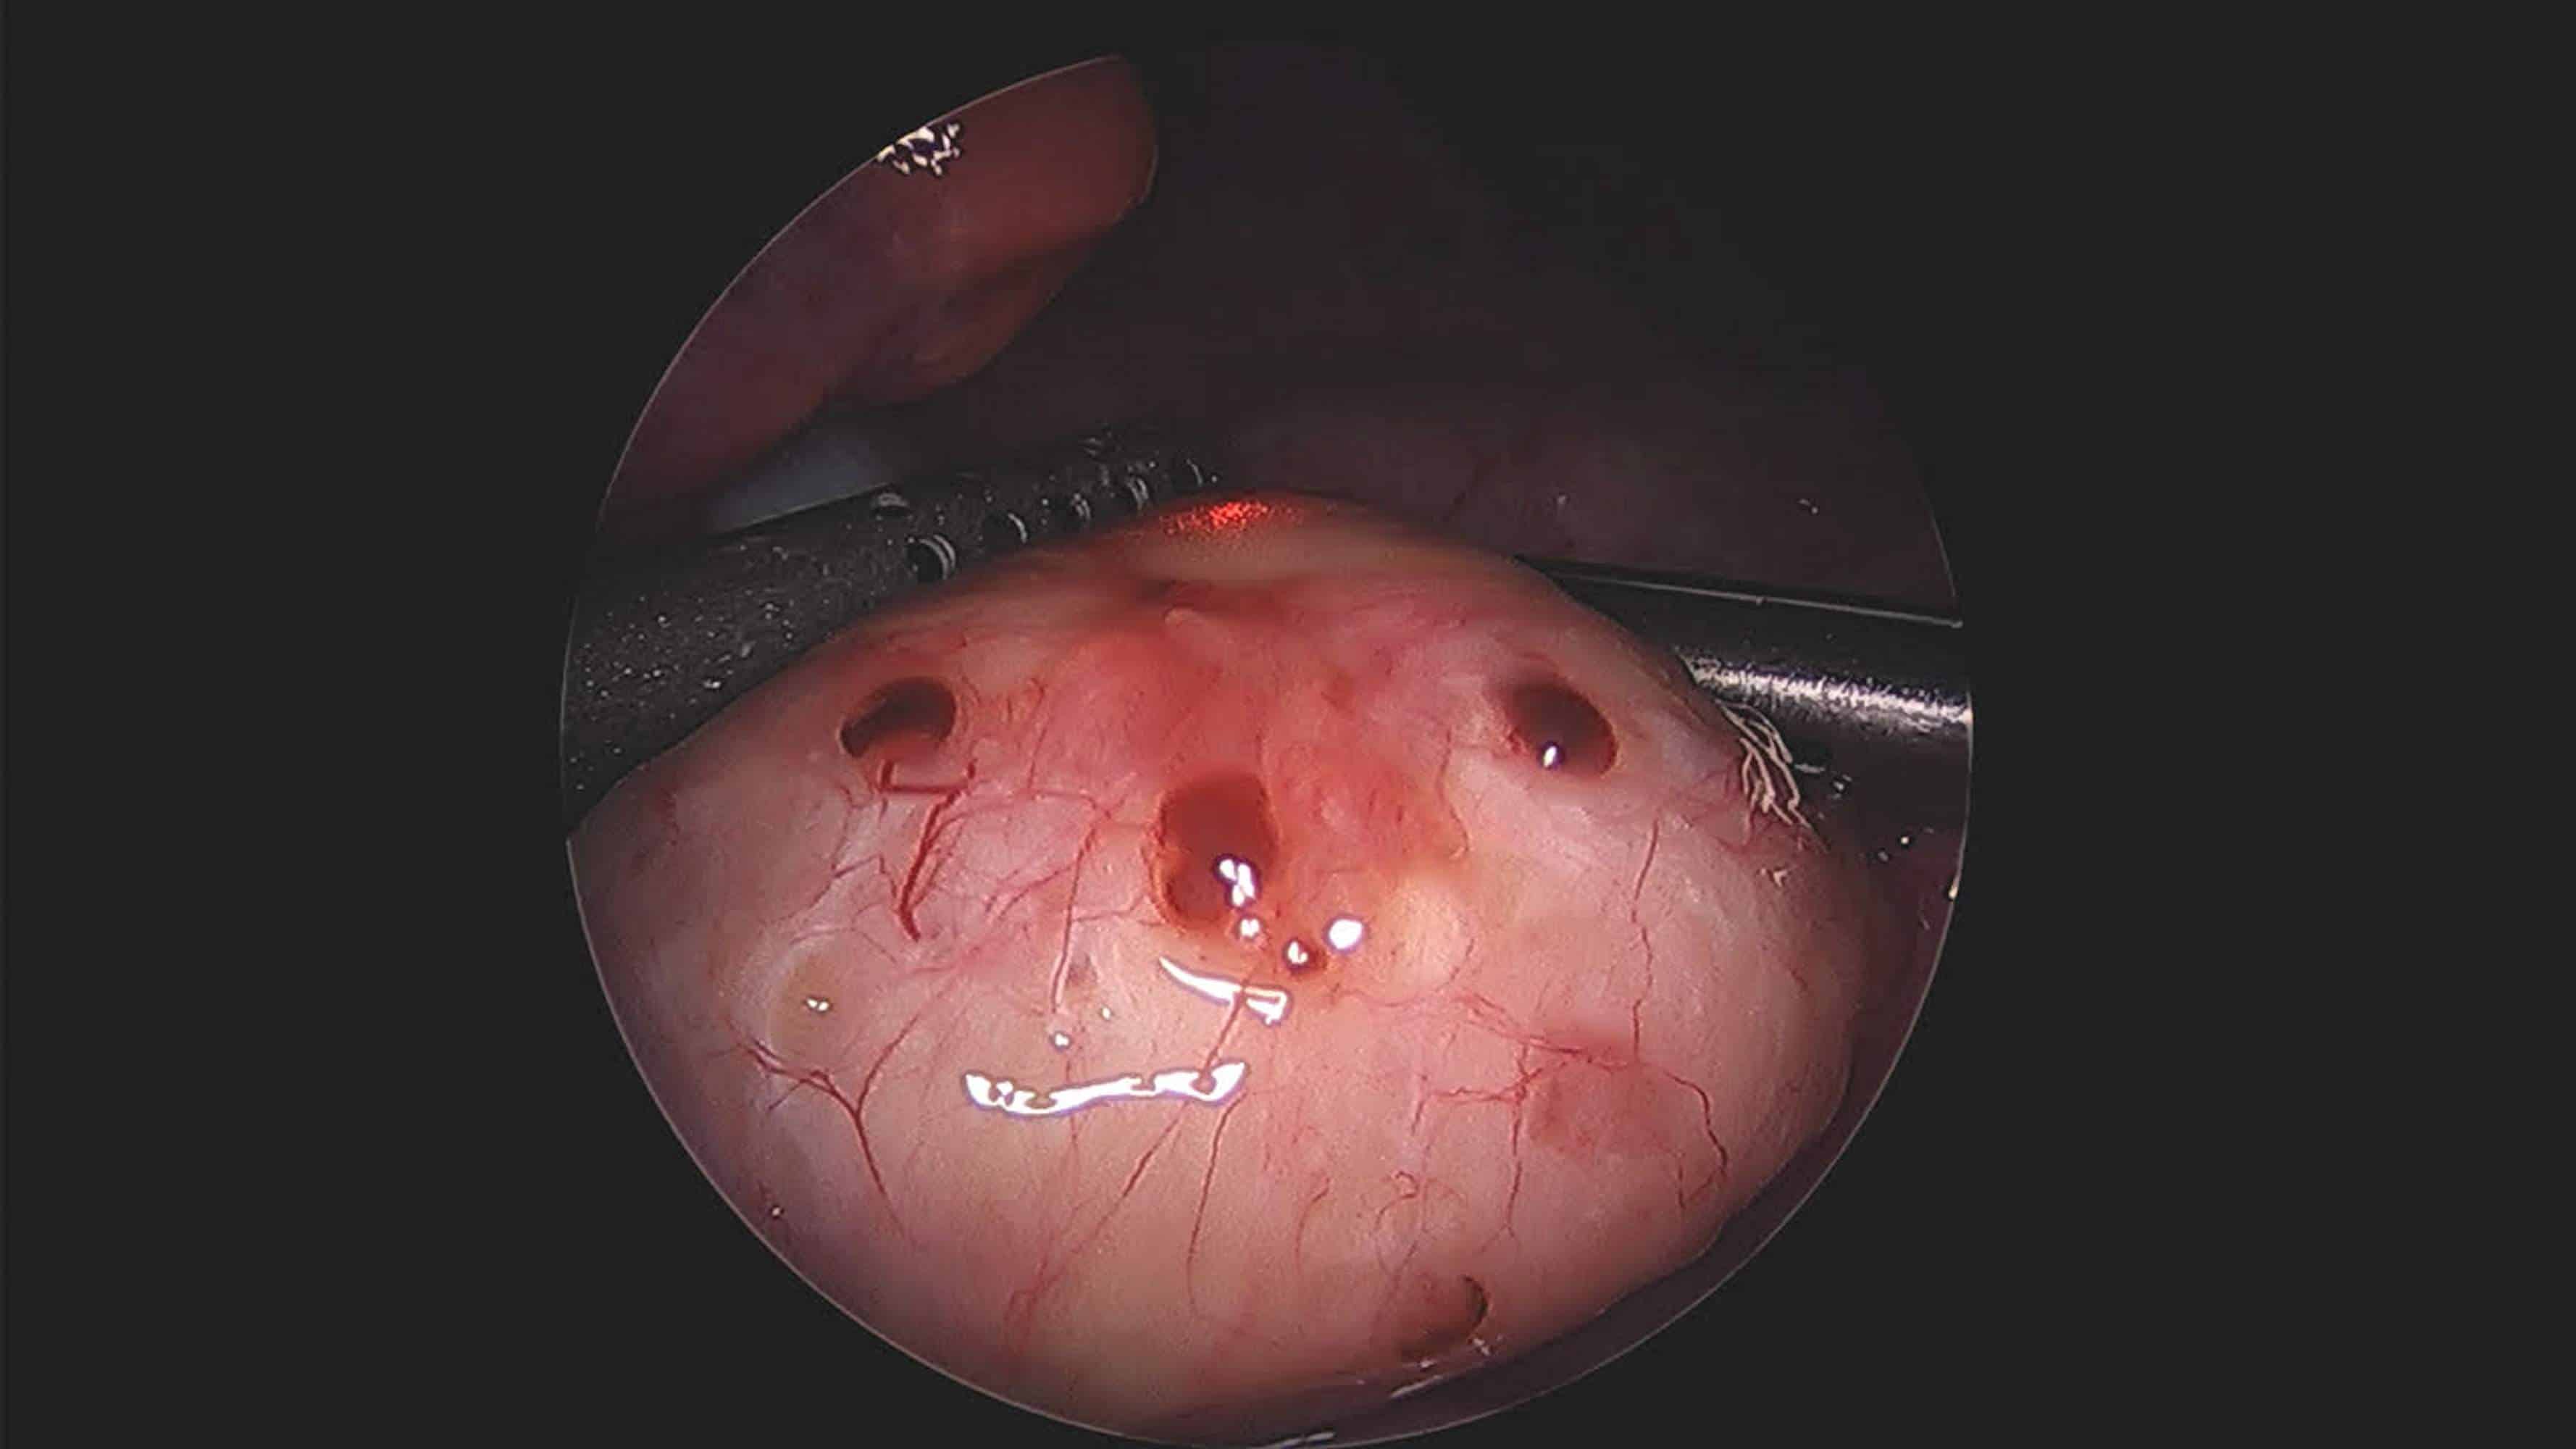

“L’endometriosi è la presenza di endometrio al di fuori della cavità uterina, normalmente nella pelvi, ma purtroppo ad oggi non esistono cure mediche – spiega Pietro Giulio Signorile, presidente della Fondazione Italiana Endometriosi – si possono combattere i sintomi con terapie ormonali, alimentazione antinfiammatoria e integratori che, riducendo infiammazione e dolori, incidono sulla percentuale di crescita della malattia. E in questo senso un ruolo importante lo gioca la diagnosi precoce: non bisogna infatti trascurare l’impatto fisico, emotivo e relazionale della malattia che si ripercuote sul lavoro e nei rapporti sociali e con il partner. Per questo la Fondazione nell’ambito dell’attività di ricerca, supporto e informazione, persegue l’obiettivo di sostenere le donne nel loro percorso di cura, promuovere studi e aumentare la conoscenza sulla malattia per rendere l’endometriosi di pari dignità rispetto alle altre malattie sociali, e ridurre le differenze tra le malattie croniche e di genere”.